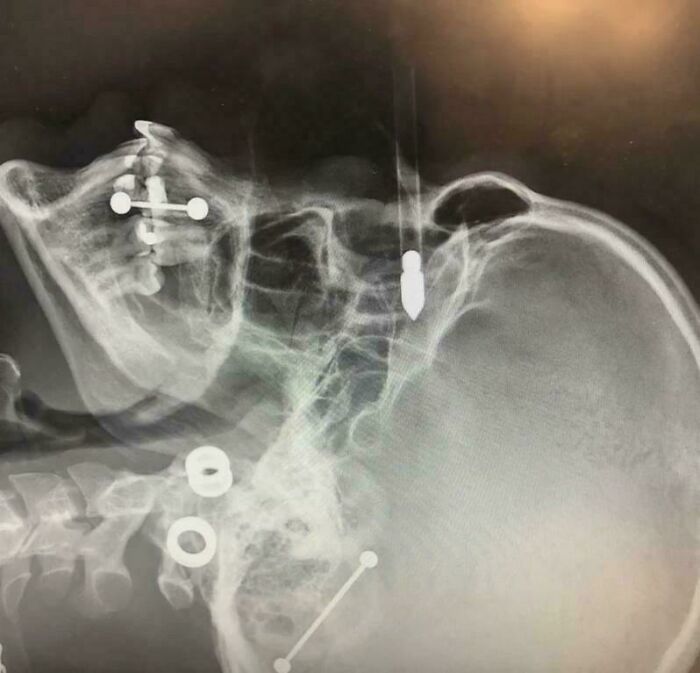

#15 Chainsaw Accident On X-Ray

Image credits: Unusualway